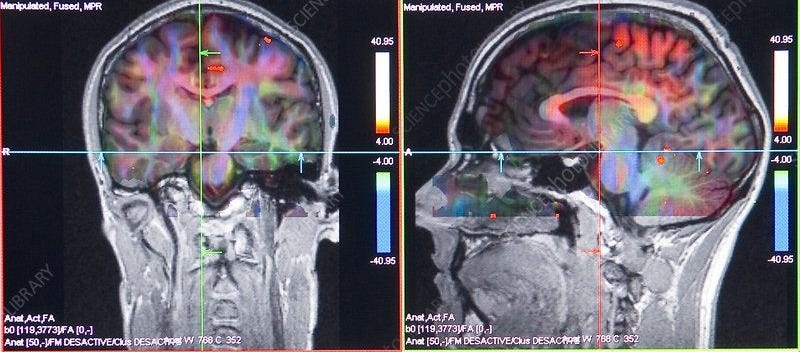

WHAT IT’S ACTUALLY DOING TO YOUR BRAIN

here’s the neuroscience.

every time you scroll and a new video loads, your brain releases a small pulse of dopamine.

not from the content itself but from the anticipation of it.

the half-second before the next video plays. that tiny moment of “what will this be?”

that’s your brain on a neurological slot machine.

same mechanism as gambling. same mechanism as pulling a lever.

variable reward. unpredictable outcome. maximum dopamine response.

tiktok didn’t stumble onto this by accident. the algorithm was designed to maximize the unpredictability of what comes next, because unpredictability is what keeps the dopamine loop running.

and the more you feed that loop, the more your brain recalibrates around it.

your prefrontal cortex, the region handling sustained attention, impulse control, and deep cognitive work, gets progressively weakened by short-form content consumption.